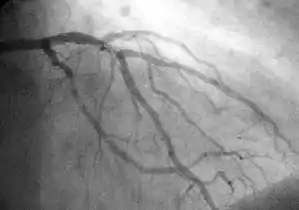

A قسطرة الشريان التاجي that shows the LMCA, LAD and LCX.